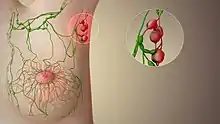

The sentinel lymph node is the hypothetical first lymph node or group of nodes draining a cancer. In case of established cancerous dissemination it is postulated that the sentinel lymph nodes are the target organs primarily reached by metastasizing cancer cells from the tumor.

The spread of some forms of cancer usually follows an orderly progression, spreading first to regional lymph nodes, then the next echelon of lymph nodes, and so on, since the flow of lymph is directional, meaning that some cancers spread in a predictable fashion from where the cancer started. In these cases, if the cancer spreads it will spread first to lymph nodes (lymph glands) close to the tumor before it spreads to other parts of the body. The concept of sentinel lymph node surgery is to determine if the cancer has spread to the very first draining lymph node (called the "sentinel lymph node") or not. If the sentinel lymph node does not contain cancer, then there is a high likelihood that the cancer has not spread to any other area of the body.[2]

The concept of the sentinel lymph node is important because of the advent of the sentinel lymph node biopsy technique, also known as a sentinel node procedure. This technique is used in the staging of certain types of cancer to see if they have spread to any lymph nodes, since lymph node metastasis is one of the most important prognostic signs. It can also guide the surgeon to the appropriate therapy.[3]